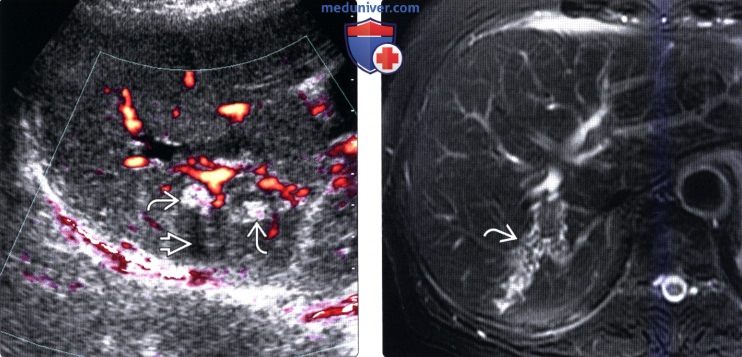

Фотографии и изображения, связанные с симптомами первичного склерозирующего холангита